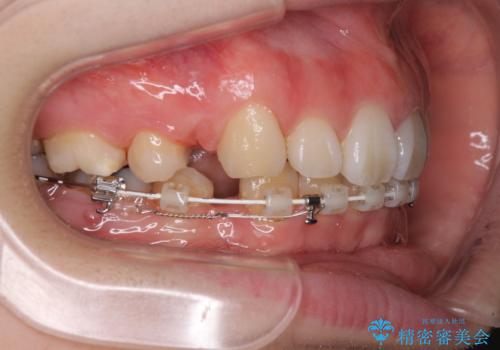

- ハーフリンガル

目立たない装置が希望であったため、上顎が裏側装置である、ハーフリンガル装置を選択されました。

当初予定では3年以上かかるとお伝えしておりましたが、スムーズに歯列が整い、2年強で終了することができました。